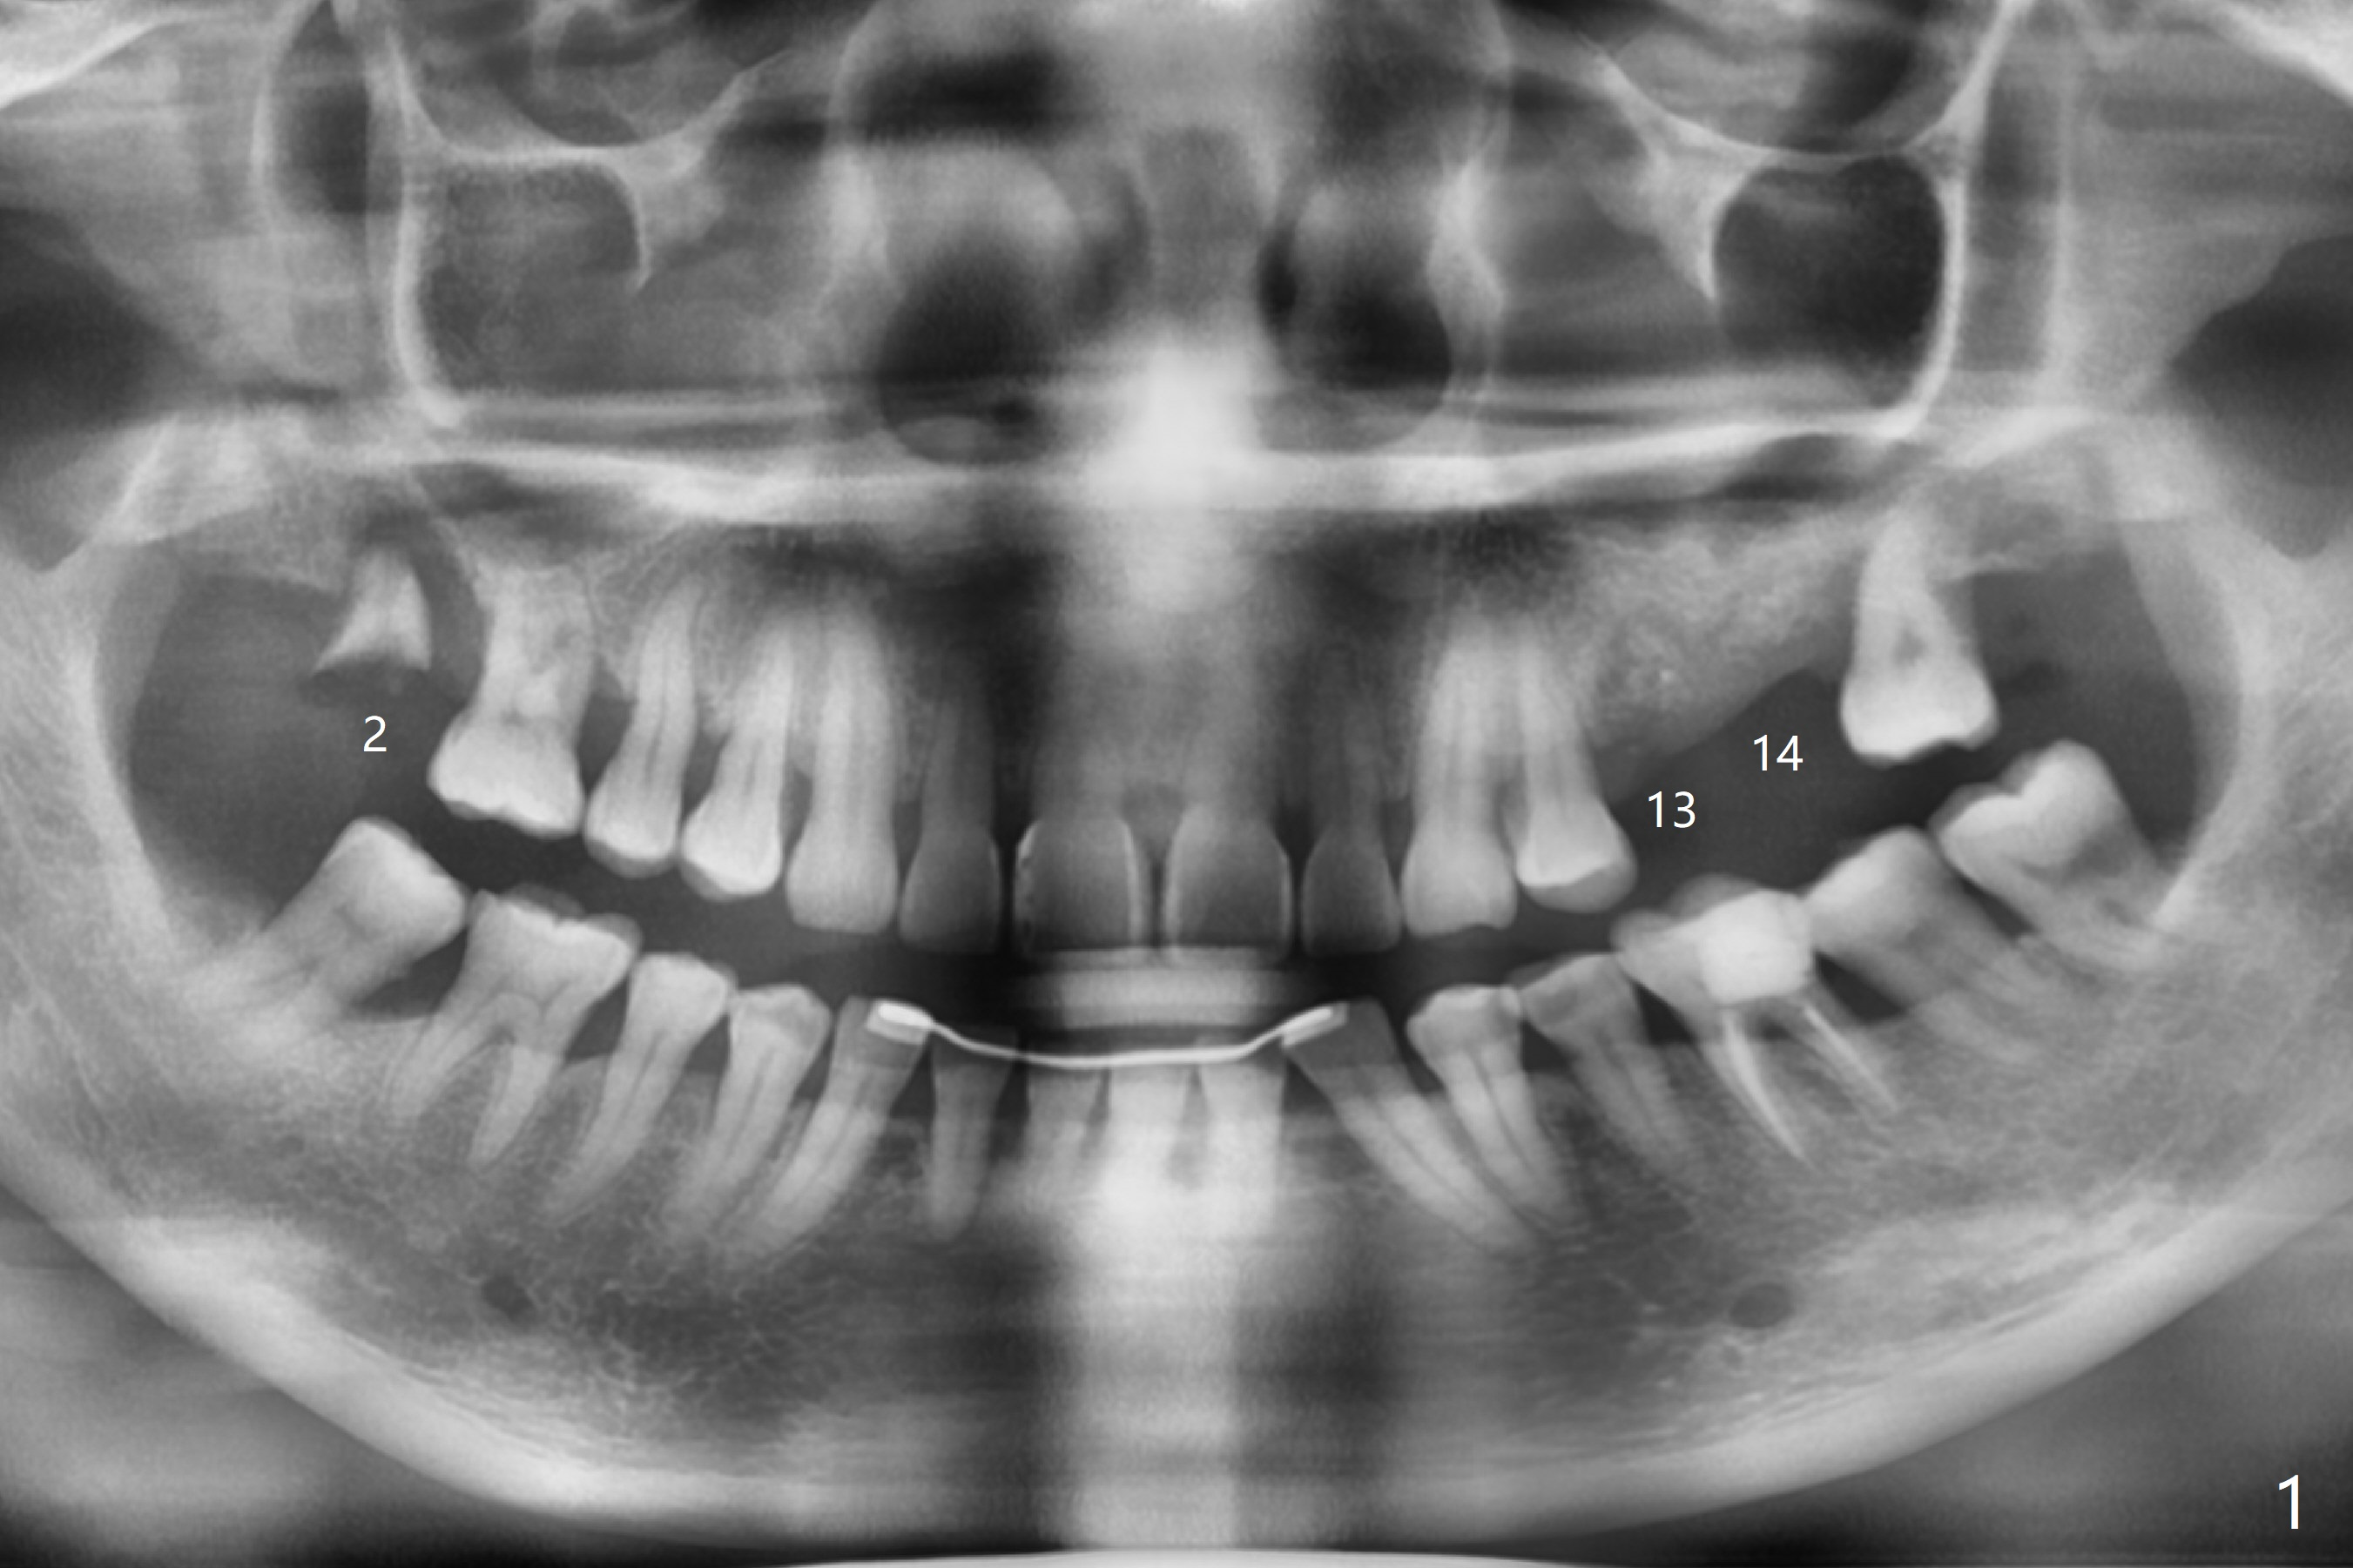

A 51-year-old woman with apparent chronic periodontitis (Fig.1) has the teeth #13 and 14 extracted with socket preservation in her home country 3 months earlier (Fig.3,4). The bone height associated with the residual roots at #2 is short; a 5x7.3 mm implant seems to be appropriate (Fig.2). Use Magic expanders and sinus lifter. The implant will be Magicore or consistent with those at #13 and 14. Prepare 2 pieces of PRF membrane for sinus lift and buccal defect. Osteotomy at #13 should be palatal (Fig.3 red line instead of blue one) to obtain more of the apical native bone for primary stability. Prescribe Augmentin after sinus lift. Osteotomy at #14 should be a little bit more distal because of the mesial shift of the tooth #15 (Fig.4). Early provisional to hold the edentulous space and limited ortho may be required. A guide will be made for #13 and 14.